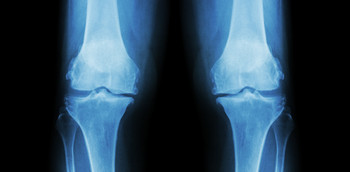

Artrografía, Artroct y Artrorm

La artrografía es el estudio radiológico de una articulación tras la inyección de contraste intraarticular.  El pequeño tamaño de algunas de las estructuras intraarticulares, así como del cartílago intraarticular, junto con el aumento de las técnicas quirúrgicas, ha...